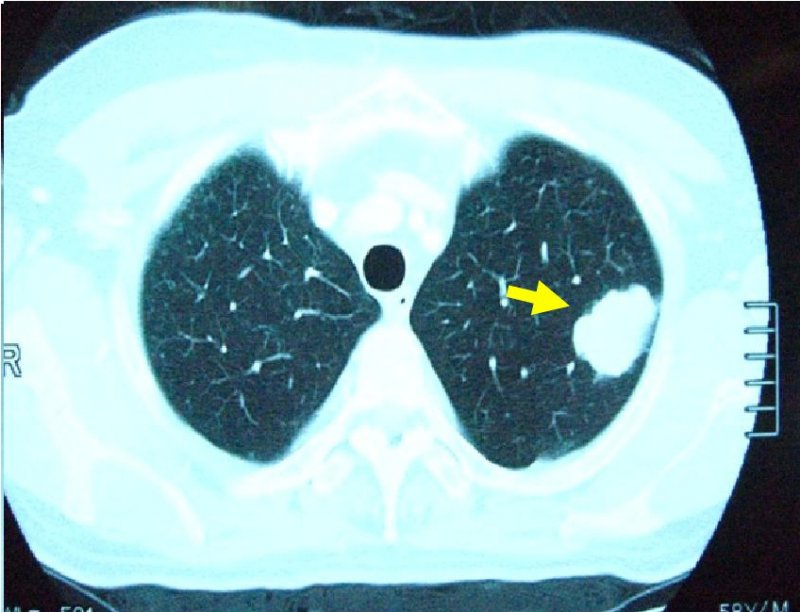

左肺癌の画像所見

胸部XP(左上肺野に腫瘤影あり)

胸部CT